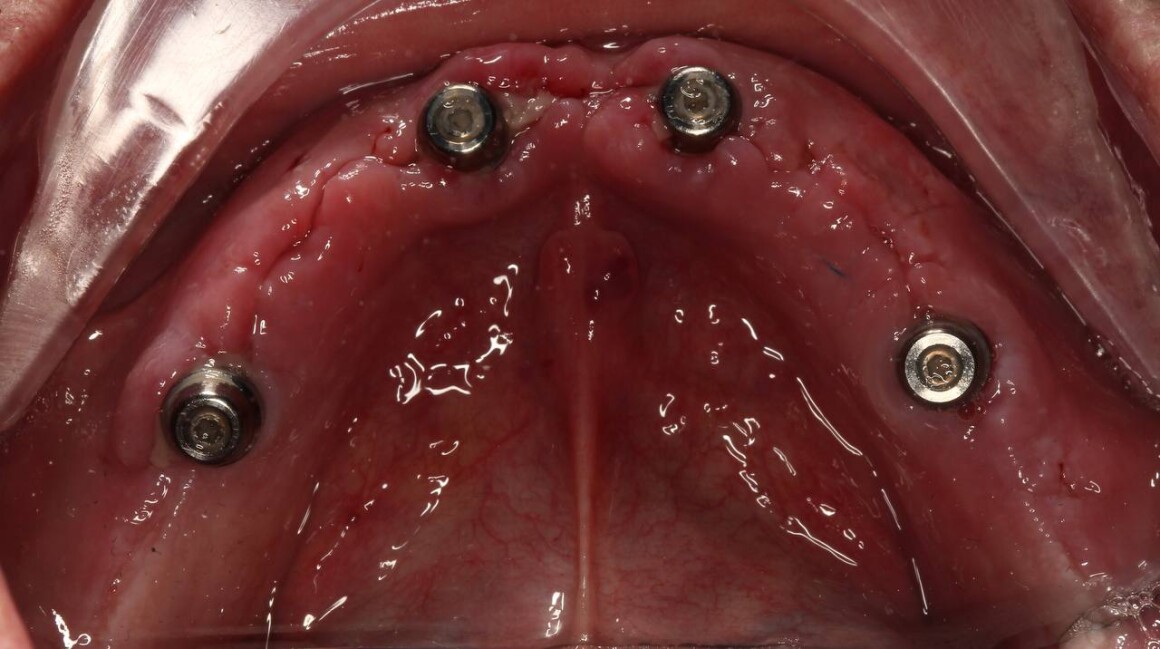

Адаптационные протезы ALL on 4

Имплантация ALL on 4 на верхней и нижней челюстях в день операции